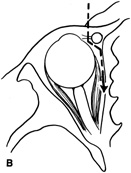

Once the outer surface of the lateral rim has been exposed, the periorbita along the mesial surface of the lateral wall is similarly elevated posteriorly within the orbit so that the bony lateral orbital rim can be completely bared along its external and internal surfaces. The periorbita is tightly adherent at the inner orbital rim (arcus marginalis), especially over the lateral orbital tubercle. Periorbital elevation in this area must be performed carefully to avoid buttonholing and prolapse of orbital fat. Once the elevation has proceeded along the inner surface posterior to the lateral orbital tubercle, the periorbita elevates quite freely from the bone. The zygomaticotemporal and zygomaticofacial neurovascular bundles are encountered about 1 cm posterior to the rim (Fig. 7). Transecting the neurovascular bundles results in a small area of postoperative hypesthesia over the lateral rim. These bundles usually are cut with a unipolar cautery to allow periorbital elevation to continue back to the inferior orbital fissure. The periorbita enters the inferior orbital fissure at the junction of the lateral wall and floor and is a landmark to establish the depth of dissection along the inner surface of the lateral rim.

Fig. 7. Coronal schematic view demonstrating major vessels penetrating periorbita and traversing the extraperiosteal space that may be encountered during periorbital elevation. (A, zygomaticotemporal artery; B, zygomaticofacial artery; C, communicating branch of infraorbital artery: D, supraorbital artery: E, posterior ethmoidal artery: F, anterior ethmoidal artery.)